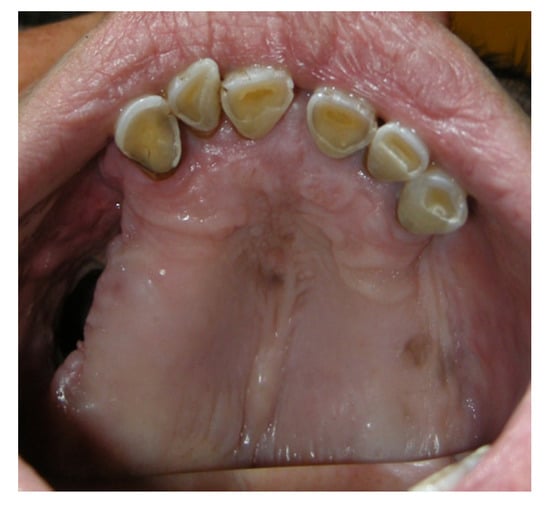

3.1.1. Case 1: A.R.

| A.R | X | * | 5 | 1 | ||